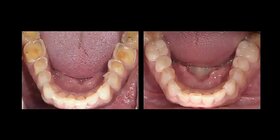

Starcie polega na zmniejszeniu grubości, a w konsekwencji utracie zewnętrznych warstw tkanek. Każdy z nas w ciągu swojego życia ściera zęby. Jednakże niestety coraz częściej pojawia się problem uogólnionego patologicznego ścierania. Dotyczy on często młodych ludzi i prowadzi nie tylko do problemów estetycznych, ale również zaburza funkcję żucia. Stwarza również inne dolegliwości: wzmożoną wrażliwość na zimne, gorące i kwaśne pokarmy, przebarwianie się uzębienia. Stają się ostre, kaleczą tkanki miękkie. Na skutek zmniejszenia wysokości zwarcia pojawiają się problemy w stawie skroniowo-żuchwowym, często ból w okolicy uszu, twarzy. Wszystko to sprawia, że konieczna jest odbudowa zęba, którą wykonujemy w naszej klinice w Lublinie.

W naszym Centrum stomatologicznym w Lublinie leczenie rozpoczynamy od ustalenia przyczyny starcia zębów. W tym celu przeprowadzamy kilkuetapowe badanie diagnostyczne, zwane deprogramacją Koisa. Polega ona na znalezieniu i rejestracji tzw. Relacji Centralnej, czyli takiego położenia żuchwy, które jest niezależne od działania mięśni. (Gwarantuje nam ono długoczasowe, bezawaryjne funkcjonowanie wykonanej rekonstrukcji zwarcia). W kolejnym etapie analizujemy i oceniamy zwarcie pacjenta na modelach gipsowych w artykulatorze i planujemy leczenie. Przy niewielkim stopniu starcia zębów często postępowanie sprowadza się do korekty zwarcia. W zaawansowanym stopniu konieczna jest odbudowa utraconych tkanek zębów. Stosowane są tu metody zachowawcze (odbudowa specjalnym, dedykowanym materiałem kompozytowym o twardości równej do twardości szkliwa) oraz metody protetyczne tzn. onlye, licówki, korony.

Albo nadbudowujemy zęby materiałem do odbudowy zwarcia (specjalny kompozyt o twardości i śieralności równej tkankom zęba) lub wykonujemy licówki okluzyjne ceramiczne. Leczenie prowadzone jest najczesciej po procesie deprogramacji aby efekt był możliwie jak najbardziej trwały od 250- kompozyt, do 2000- lic. cyrconowa kompozyt- na 1 wizycie, Licówka- kilka dni nieStarte zęby jak odbudować?/Jak zregenerować starte zęby? ▶